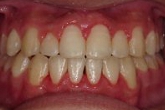

CASE5

小学1年の頃から前歯の噛み合せが逆でした。

同級生が通っていたので来ました。

(11歳/男性)↓

概要・担当医コメント:反対咬合・前歯部咀嚼障害↑

/マルチブラケット装置/非抜歯/動的治療期間24ヶ月(25回)/費用概算:60万円

治療前は虫歯のコントロールが難しい状態でしたが,矯正治療を開始してからは歯磨きを丁寧にしてくれるようになり,甘味摂取習慣の改善も行って頂いた効果があり,その後の虫歯の発生は無く現在に至っています.